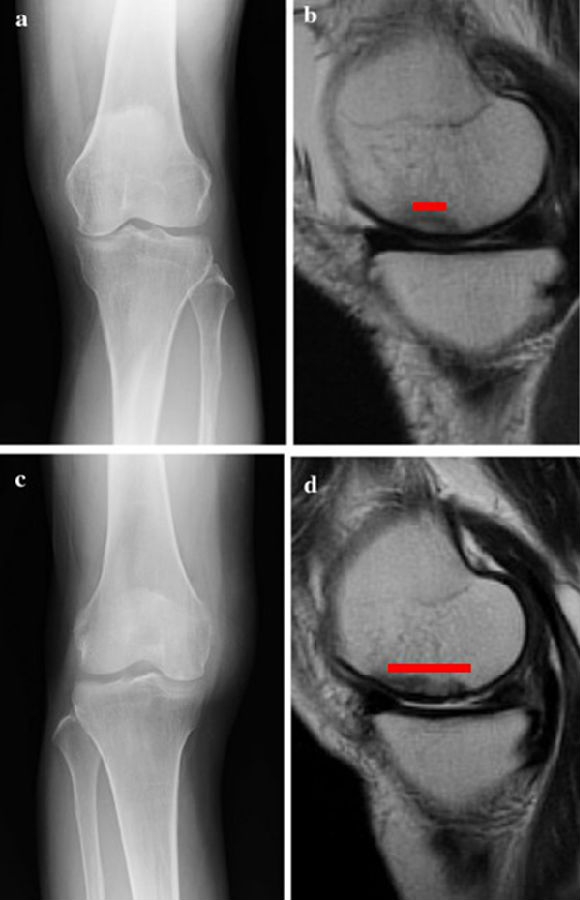

a.患者,59岁女性,AP侧位片显示SONKⅠ期,FTA<180°;b.MRI T2显示病变深度<20mm,患者出现症状1年后保守治疗;c.75岁女性,X线显示SONKⅠ期,FTA>180°;d. MRI T2显示病变深度>20mm,患者于症状出现后11周行手术治疗